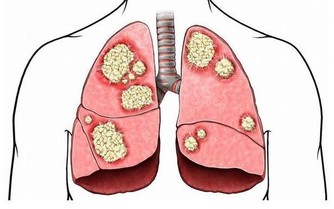

猝死主要分為三類導致猝死的情形有許多種,大多與心臟有關,叫心源性猝死,另有腦幹出血、中暑等其他原因也會導致很短時間內死亡。